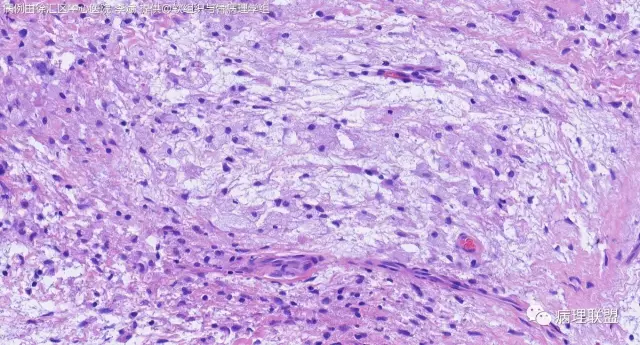

关节旁粘液瘤,肿瘤中间明显有腱鞘囊肿结构,又发生在关节处!强烈提示为关节旁粘液瘤,部分病例可以呈分叶结构!平时多加观察腱鞘囊肿囊壁常可见粘液变性!范围一广就成粘液瘤样。

@周泉 周老师您好,李斌老师第一个病例里细胞都是上皮样的包浆宽的,嗜酸,粘液瘤细胞细胞梭的星形的,所以我考虑是神经鞘的了,您觉得粘液瘤细胞也可以这种形态吗?

@左淑英 部分应该是组织细胞